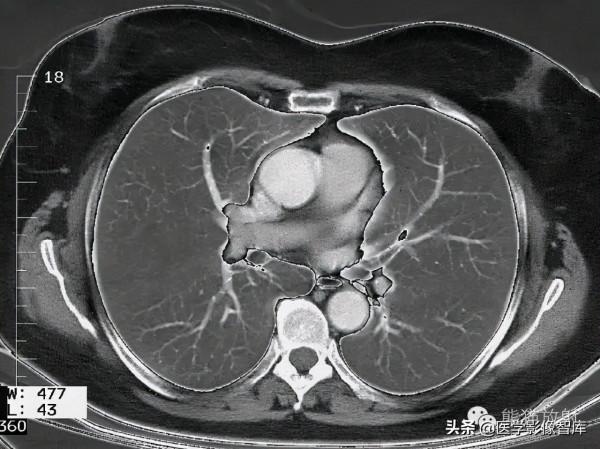

第八層:肺動脈幹水平

1. Latissimus dorsi muscle 背闊肌

2. Long thoracic nerve 胸長神經

3. Serratus anterior muscle 前鋸肌

4. Glandular tissue of the breast and nipple 乳腺腺體及乳頭

5. Right lung 右肺

6. Pectoralis major muscle 胸大肌

7. Right pulmonary artery 右肺動脈

8. Superior vena cava 上腔靜脈

9. Internal thoracic artery and vein 胸內動脈、靜脈

10. Ascending aorta 升主動脈

11. Sternum 胸骨

12. Pulmonary trunk 肺動脈幹

13. Rib (costal cartilage) 肋骨(肋軟骨)

14. Left pulmonary vein 左肺靜脈

15. Left atrium 左心房

16. Intercostal muscle 肋間肌

17. Rib 肋骨

18. Teres major muscle 大圓肌

19. Infraspinatus muscle 岡下肌

20. Scapula 肩胛骨

21. Trapezius muscle 斜方肌

22. Right inferior lobar bronchus 右肺下葉支氣管

23. Erector spinae muscle 豎脊肌

24. Thoracic vertebra 胸椎

25. Spinal cord 脊髓

26. Azygos vein 奇靜脈

27. Thoracic duct 胸導管

28. Esophagus 食管

29. Descending aorta 降主動脈

30. Left inferior lobar bronchus 左肺下葉支氣管

31. Rhomboid muscle major 菱形肌

32. Left lung 左肺

33. Subscapularis muscle 肩胛下肌